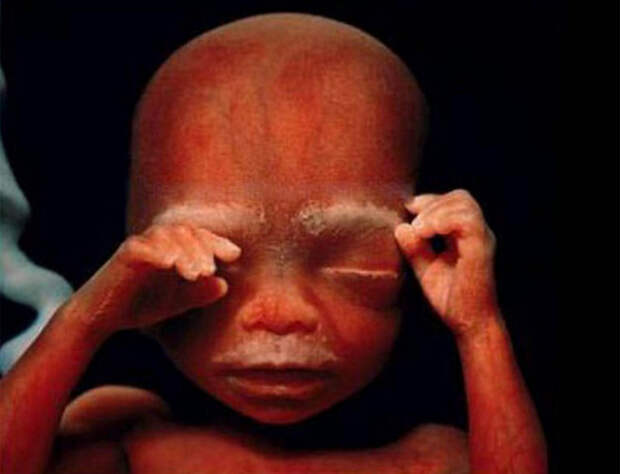

В конце восьмой недели будущий малыш немного смахивает на милого инопланетянина.  В 16 недель маленький эмбрион уже пытается исследовать окружающее его пространство при помощи рук.

В 16 недель маленький эмбрион уже пытается исследовать окружающее его пространство при помощи рук.  Такие крошечные суставы и будущие косточки.